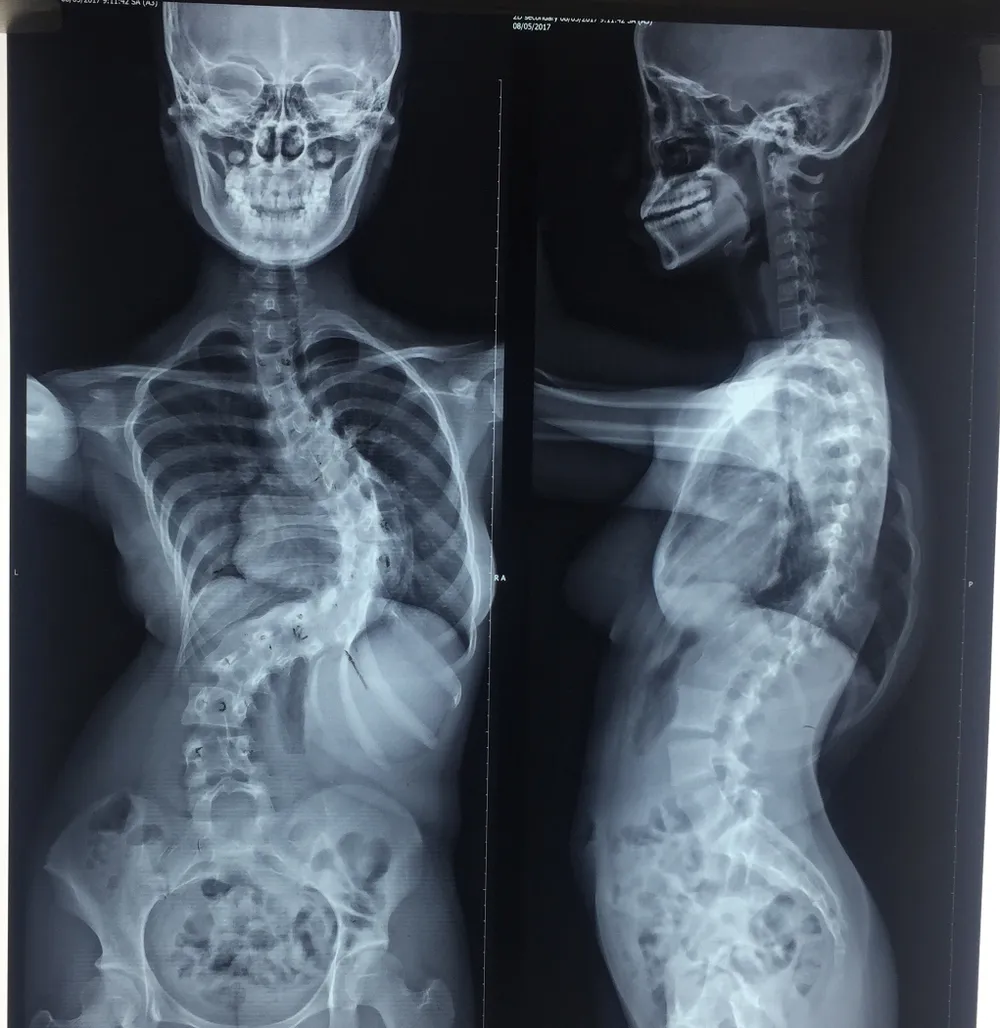

Nữ sinh sau khi được nắn chỉnh cột sống. Ảnh: H.LAN

Bệnh nhân đã được nắn chỉnh hàn xương, bắt 21 ốc chân cung, bốn thanh nối dọc và ngang để nắn chỉnh lại cột sống. Trong quá trình mổ, các bác sĩ đã sử dụng máy lọc máu hoàn hồi có khả năng lọc lại lượng máu đã mất để truyền lại cho bệnh nhân nên hạn chế tối đa lượng máu chảy. Ca mổ đã nắn chỉnh được 64% cột sống cho nữ sinh, chỗ cong nhất từ 110 độ giảm còn 40 độ. Chiều cao của nữ sinh cũng tăng lên được 7cm, từ 1m48 lên 1m55. Hiện nữ sinh đã ngồi dậy và đi lại được.

Cũng theo các bác sĩ, khi bước vào tuổi dậy thì, khung xương phát triển khiến bệnh càng diễn tiến nặng hơn. Lẽ ra với độ cong của cột sống hiện tại, em phải được chỉ định mổ từ sớm (khi mới 40 độ), lúc đó khả năng để lại di chứng sẽ ít hơn. Tuy nhiên, phải mất chín tháng cải thiện tình trạng suy dinh dưỡng, mạch đập nhanh cho nữ sinh, ca mổ mới được tiến hành vào ngày 26-12.